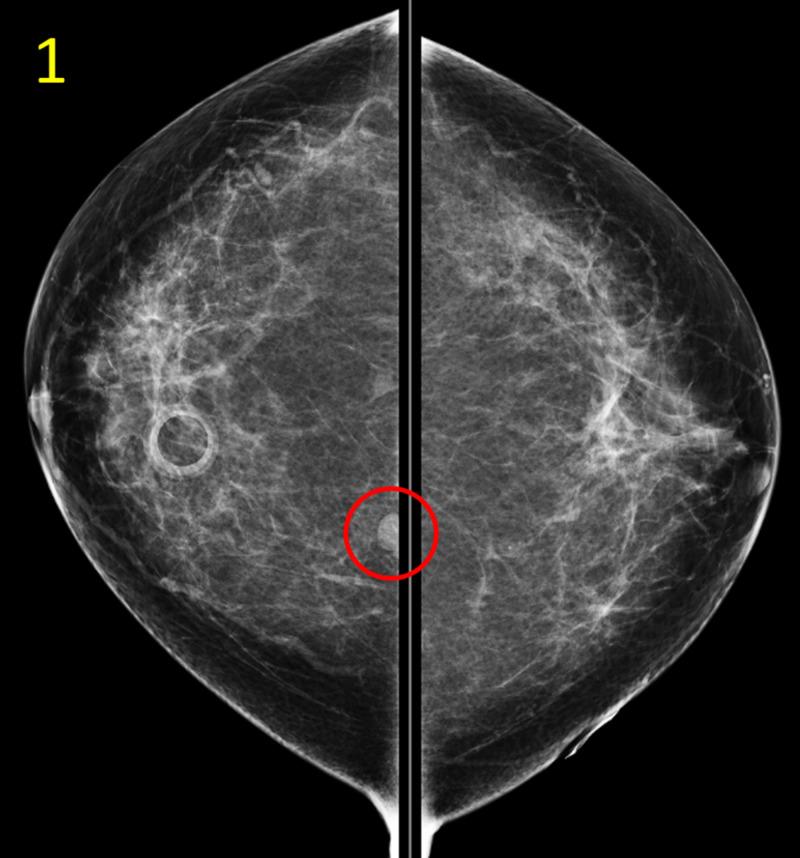

Renal cell carcinoma (RCC) defines a varied class of primary renal neoplasms which arise from the renal cortex. Because RCC often progresses silently to a very advanced metastatic stage, the majority of RCC cases are diagnosed either incidentally on abdominal imaging or upon presentation of invasive disease at metastatic sites. This case profiles a 57-year-old woman with distant history of resected RCC who presented with a posterior breast mass that was diagnosed as metastatic recurrence of RCC through mammogram, ultrasound, and core biopsy. Although the breast is an unusual site for metastasis, clinicians should consider metastatic RCC as a possible etiology when evaluating women with history of RCC and a newly discovered breast mass.

肾细胞癌(RCC)是一类起源于肾皮质的原发性肾脏肿瘤。由于肾细胞癌通常在无声无息中发展到非常晚期的转移阶段,大多数肾细胞癌病例是在腹部影像学检查时偶然发现的,或者是在转移部位出现侵袭性疾病时才被诊断出来。本病例介绍了一名57岁女性,她有肾细胞癌切除史,此次因乳腺后部肿块就诊,通过乳房X线摄影、超声和芯针活检诊断为肾细胞癌转移复发。尽管乳腺是不常见的转移部位,但临床医生在评估有肾细胞癌病史且新发现乳腺肿块的女性时,应考虑转移性肾细胞癌作为可能的病因。